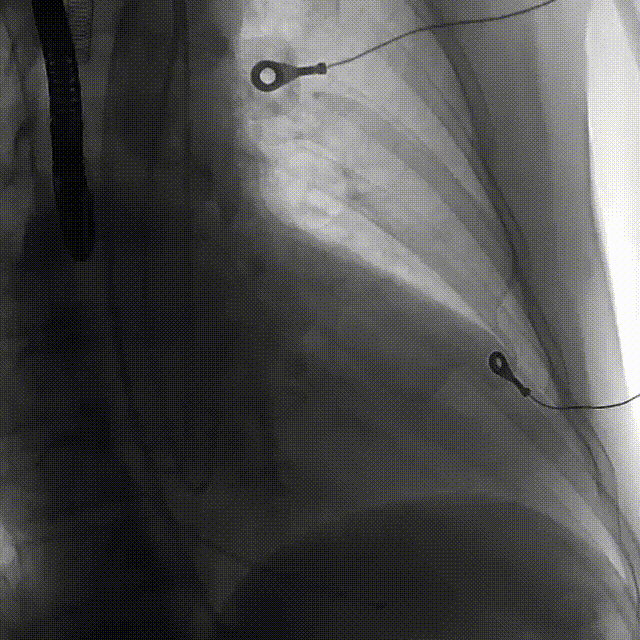

主动脉弓角度与宽度可,心脏水平夹角68°,横位心。

该患者为一例合并升主动脉瘤的大角度横位心重度AS患者。

3. 升主动脉扩张明显,合并大角度横位心,器械进入走行时存在一定困难,须注意防范血管并发症风险;

3. 患者主动脉弓距和夹角可,升主动脉扩张明显,合并大角度横位心,器械进入时应尽量轻柔,可使用抓捕器辅助器械操作,避免引起血管损伤。并注意器械于左室内的操作;

5.根据术前评估及球囊预扩情况,选择23mm沛嘉TaurusElite瓣膜进行植入,抓捕器辅助下输送器头端进入左室,零位定位